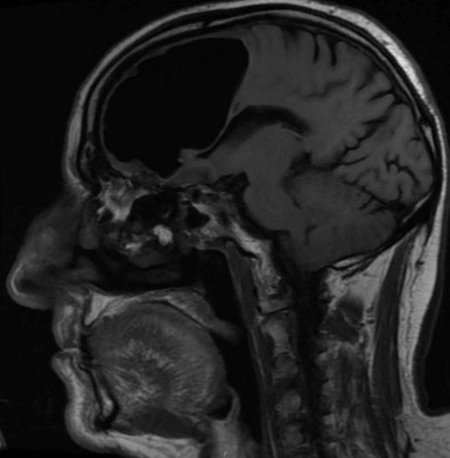

ماده مغزی در جمجمه بيمار ناپديد نشده است

نتيجه سی تی اسكن گيج كننده بود، حفره ای بزرگ و سياه به وسعت 9 سانتيمتر در لوب پيشانی سمت راست مرد ديده می شد. در مرحله بعدی مغز مرد با دستگاه MRI مورد بررسی قرار گرفت و پزشكان دريافتند ماده مغزی در جمجمه بيمار ناپديد نشده است، بلكه درون جمجمه اش حفره ای از هوا به نام پنوماتوكوئل ايجاد شده بود كه معمولا در بيمارانی ديده می شود كه دچار آسيب ديدگی صورت يا عفونت تنفسی شده اند يا در جمجمه آنها جراحی انجام شده است.

اما هيچ يک از اين عوامل در اين بيمار به ايجاد اين پنوماتوكوئل بزرگ منجر نشده بود. پزشكان همچنين در استخوان اتموئيد مغز مرد، استخوانی كه حفره تنفسی را از مغز جدا ميكند، نوعی تومور خوش خيم پيدا كردند. اين بخش آسيب ديده استخوانی باعث شده بود تا هوا به درون جمجمه نشت كرده و پديده ای به نام تاثير لوله يک طرفه ايجاد كند.